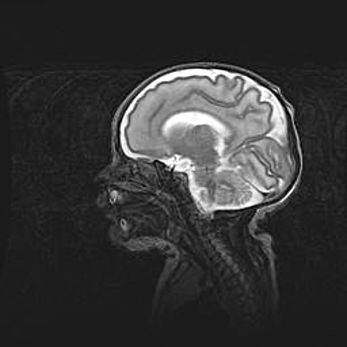

Мальформация Денди-Уокера. Киста задней черепной ямки.

Агенезия мозолистого тела.

Возраст: 2,5 месяца

Вес: 2420 г

Пол: женский

Окружность головы: 37 см

Срок гестации: 32 недели

Мальформация Денди—Уокера — редкий вид патологии ЦНС, представляющий собой врожденный порок развития каудального отдела ствола и червя мозжечка, ведущий к неполному раскрытию срединной (Мажанди) и латеральных (Лушка) апертур IV желудочка мозга. Для этогно синдрома характерна триада симптомов: гипотрофия червя мозжечка и/или полушарий мозжечка, кисты задней черепной ямки, гидроцефалия различной степени. В 70% случаев порок сочетается и с другими аномалиями головного мозга, в частности с агенезией мозолистого тела.